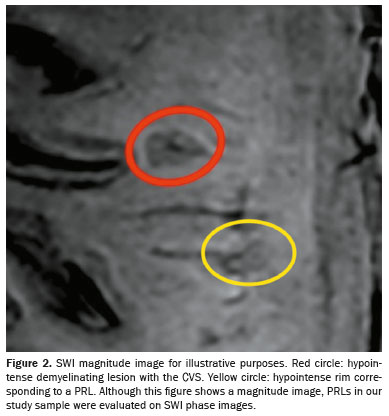

Representative lesions, including one with a CVS, are illustrated in Figures 2 and 3. As shown in Table 2, Figure 4, and Figure 5, the proportion of CVS-positive lesions was higher in the MS group than in the migraine group (61.8% vs. 10.4%).

All of the patients in the MS group had at least one PRL, whereas no PRLs were identified in the migraine and control groups. Of the 1,697 lesions identified in the MS group, 605 (35.7%) were PRLs, with a median per patient of 13.5 PRLs. Figures 2 and 3 show distinctive examples of PRLs, and Figure 6 shows the distribution of PRL locations across the groups.